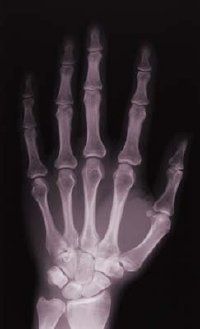

• 骨髓炎骨髓炎通常是由细菌金黄色葡萄球菌引起的。糖尿病患者和那些最近遭受了创伤复合骨折等感染的风险。慢性骨髓炎发生在感染仍然存在由于治疗不足或缺乏的治疗;这种情况可能导致骨组织感染死亡。

骨髓炎是一个美妙的词,它意味着骨感染。它通常通过直接感染发生在创伤性损伤(休息或刺伤)或通过细菌在血液中,旅行和感染骨。慢性骨髓炎发生在感染仍然存在由于治疗不足或缺乏治疗。结果,骨头没有得到充足的血液供应,和骨组织死亡。积极的治疗需要抗生素和外科手术清理死人骨头。

骨髓炎可以引起严重的疼痛在受感染的地区,以及发冷、发热、疲劳、和恶心。通常,腿部的骨头,上臂,骨盆,锁骨,脊柱都受到影响。是抗生素治疗,静脉注射,然后用嘴。